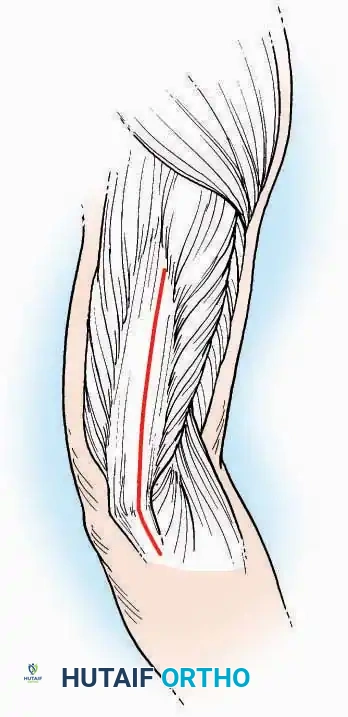

Surgical Technique:

* Incision: Begin just proximal to the IP joint and extend proximally for 5 cm, running parallel and strictly medial to the EHL tendon.

* Exposure: Divide the superficial fascia. Identify and retract the EHL tendon laterally.

* Capsulotomy: The capsule can be incised longitudinally in the exact plane of the skin incision, allowing for subperiosteal elevation of the capsule medially and laterally, preserving the vascular supply to the medial skin flap.